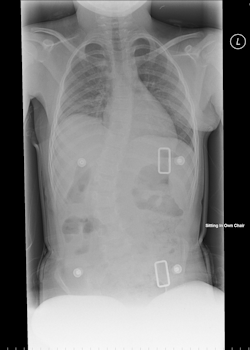

You may be sent to have x-rays of your spine and pelvis as well

This, as well as examination, will help the orthopaedic team provide the best advice to manage you as you grow, in order to prevent secondary deformity.